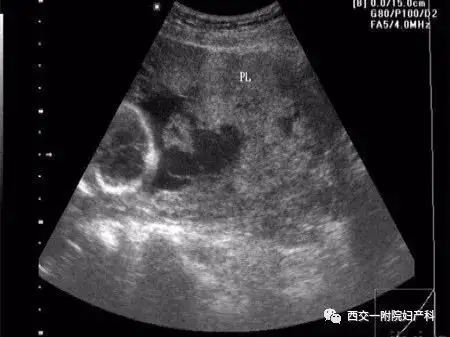

胎盘血池是什么?

胎盘血池常见不是出血不用焦虑

胎盘血池.

胎盘血池相关知识